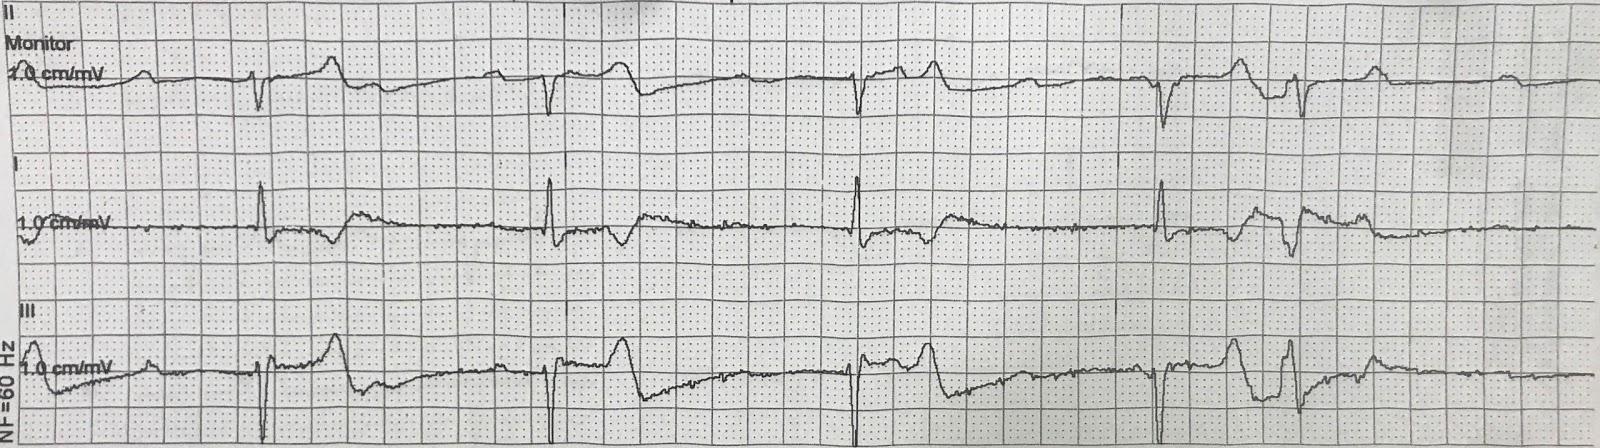

Prehospital rhythm

Steve Smith, 2017: A 60-something dialysis patient with complete heart block: ultrasound before and after treatment